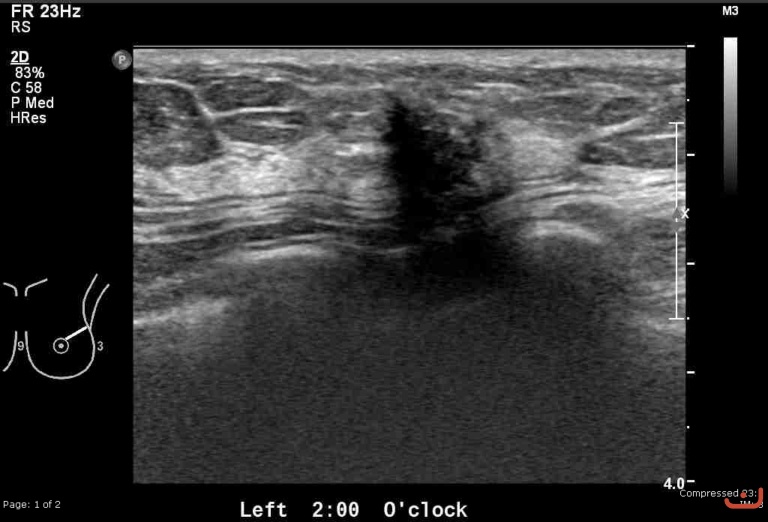

Malignant solid mass

Date

Thursday, 30 April 2015